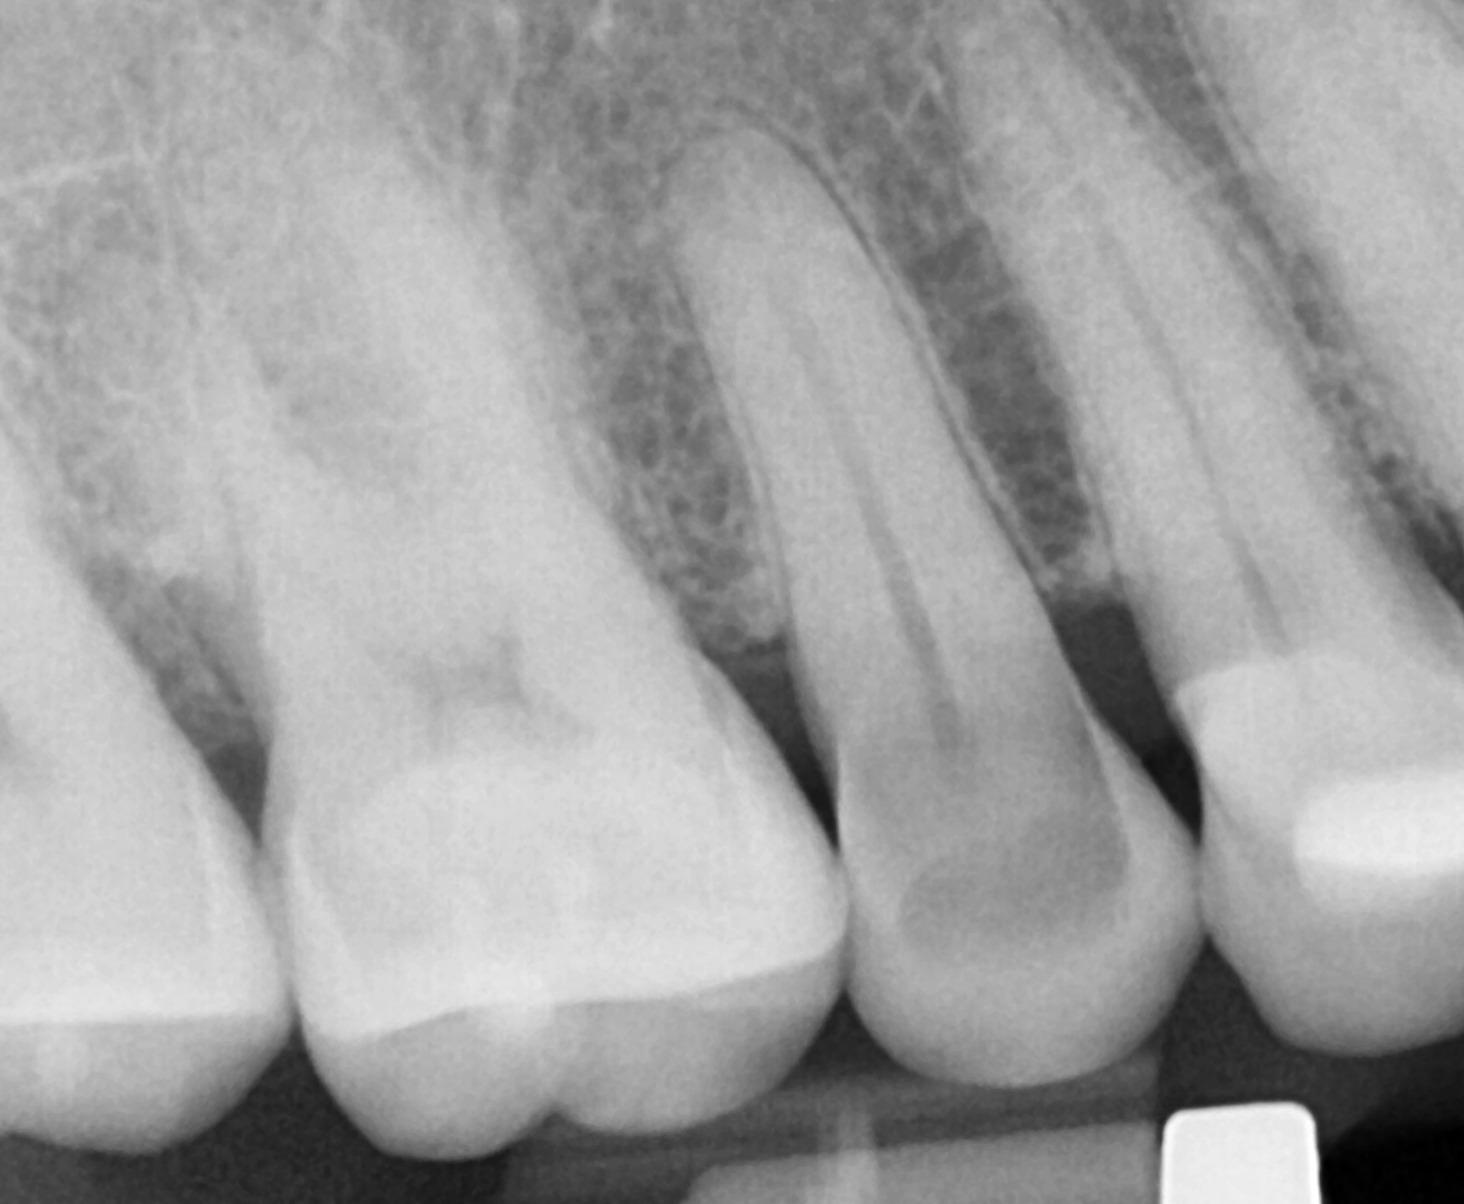

Radiographic findings:

- • No periapical radiolucency

- • Intact PDL

Pre Op PA #4

Bite wing #4 showing fracture line extending to pulp